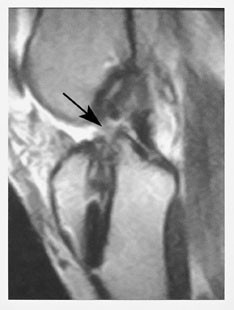

Korsbåndene er intraartikulære, men ekstrasynoviale strukturer og er viktige stabilisatorer av leddet. Det fremre (ACL), som kan variere i tykkelse, skades hyppigere enn det normalt bredere bakre (PCL). Tegn på ruptur er som for ligamenter beskrevet over (fig 7). Av og til kan det være vanskelig å avgjøre om det foreligger ruptur av fremre korsbånd. Indirekte tegn er beinkontusjon i laterale femurkondyl, spiss vinkel på bakre korsbånd og tegn på subluksasjon av tibiaplatået dorsalt.

Opererte korsbånd og korsbåndplastikker kan vurderes ved hjelp av MR (fig 8). Eventuelle skruer i henholdsvis laterale femur og mediale tibiakondyler vil ikke gi forstyrrende artefakter.